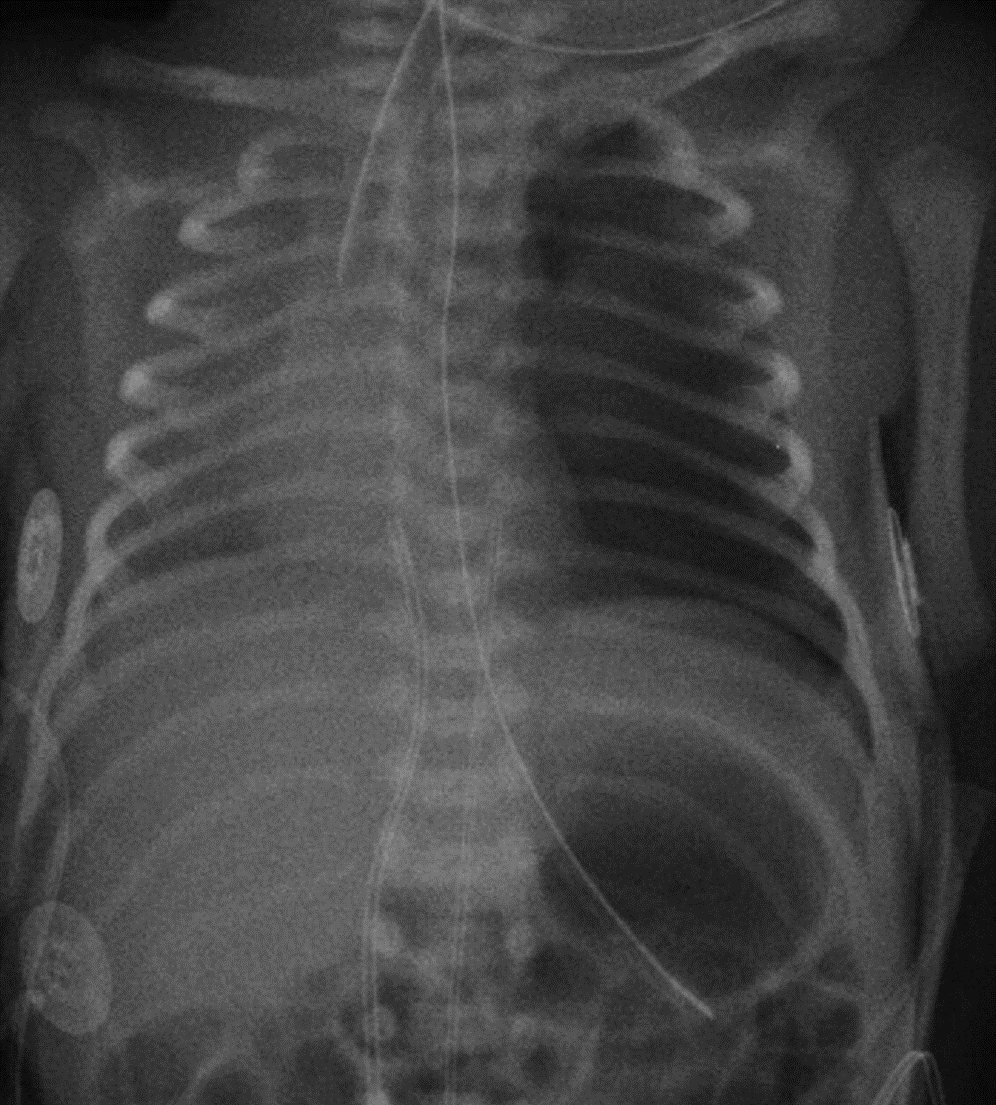

A 3 week old baby boy (born at 29/40w) is on CPAP (21% O2). He develops a rapid rise in his oxygen requirements and respiratory rate.

Examination shows reduced air entry on the left

What is the likely diagnosis?

Tension pneumothorax

Examination shows reduced air entry on the left.

Signs?

Tension pneumothorax - management